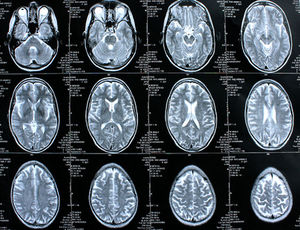

Sie sind hier: Startseite Nachrichten Gesundheit Vergessen benötigt mehr Gehirnschmalz Gehirne: Vergessen braucht mehr Aufmerksamkeit.

Gehirne: Vergessen braucht mehr Aufmerksamkeit.